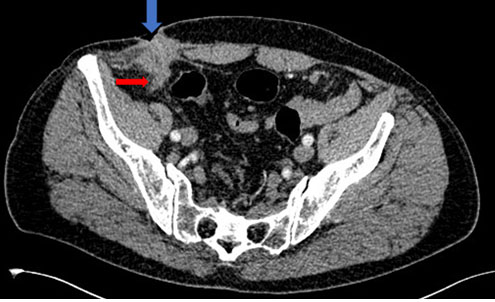

Abdominal ultrasound showed a thin-walled multiloculated cystic mass without vegetation or tissue buds. Magnetic resonance imaging was performed showing a thin-walled multiloculated cystic mass of the left liver, enhanced after injection of contrast medium, containing thin partitions with poor contrast uptake and no solid component (Figure 1A, Figure 1B, Figure 1C). The lesion was measuring 112×87 mm. It was realizing a mass effect on the adjacent intra-hepatic bile ducts without vascular invasion.

Figure 1: Hepatic MRI in (A) T1-weighted sequence, (B) T2, and (C) gadolinium-enhanced fat-suppressed turbo spin-echo T1-weighted, showing a large multiloculated cystic mass of the left liver, with a thin wall and containing thin partitions with poor contrast uptake (arrow) and no solid component.